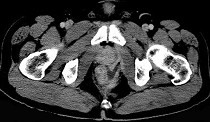

- 单项选择题男,28岁, 高热,肛门坠胀, 频有便意,直肠指诊时触及直肠粘膜下饱满, 柔软,压痛的肿块, CT检查如图,诊断为 ( )